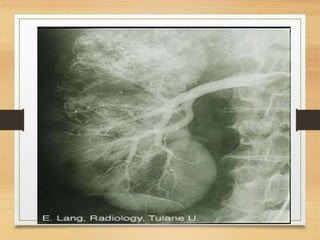

Radiological

• KUB

• U/S

• C.T

• MRU